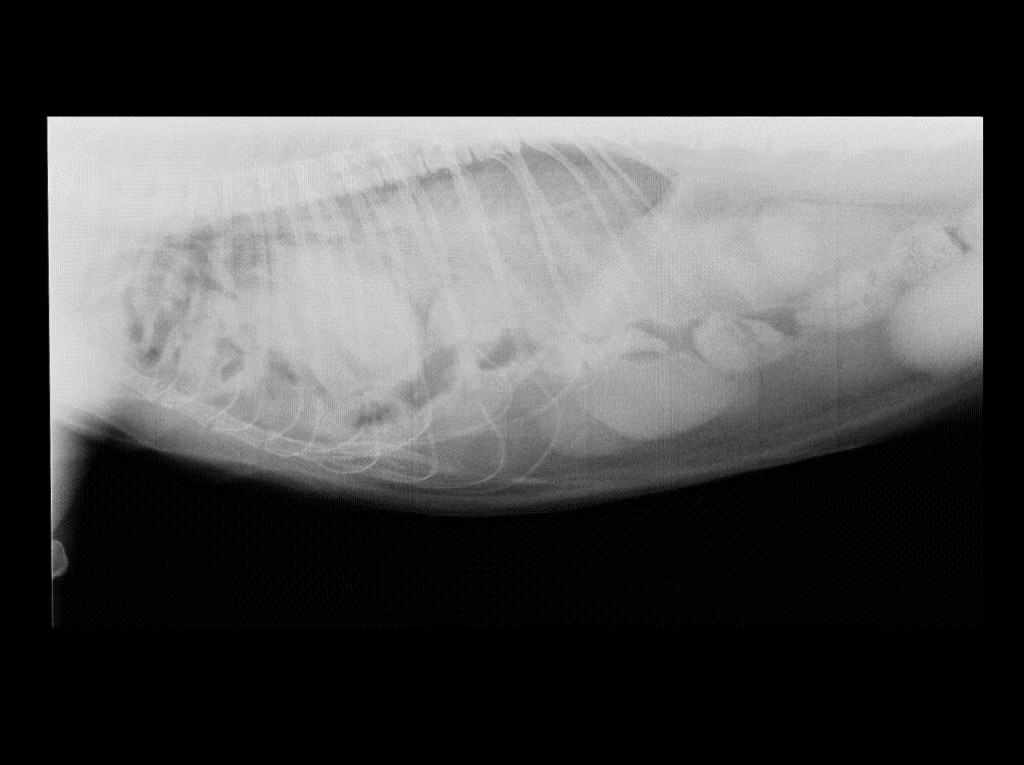

Lucas vino hace unos días a consulta porque sus dueños lo veían respirar mal. En la exploración se le notaba fatigado y jadeante. ¡Cuál fue nuestra sorpresa al hacerle una radiografía! Lucas tenía una hernia diafragmática, un desgarro en el diafragma, y la mayor parte de los órganos que debían estar en el abdomen se habían colado en el tórax, comprimiendo sus pulmones y no dejándolo respirar.

Ante la gravedad del estado de Lucas, se decidió dejarlo hospitalizado esa noche y se le sometió a cirugía al día siguiente. Se le hizo una laparotomía, accediendo así al abdomen. Lucas tenía todo el intestino, el bazo, el páncreas y gran parte del hígado dentro de la cavidad torácica. Con mucho cuidado, los órganos se fuero extrayendo y colocando en su sitio. Por último, se suturó el defecto en el diafragma con una sutura no absorbible, para evitar que la hernia vuelva a abrirse. Se le colocó también un drenaje torácico para ir sacando el aire y el líquido que pudiera acumularse entre las paredes del tórax y los pulmones durante las horas siguientes. Durante toda la cirugía, Lucas se mantuvo estable y sus constantes estuvieron dentro de la normalidad. Tras pasar la noche con oxígeno y bajo observación estrecha, fue dado de alta al día siguiente, puesto que se encontraba bien, respiraba con normalidad, y las radiografías mostraban una evolución satisfactoria.